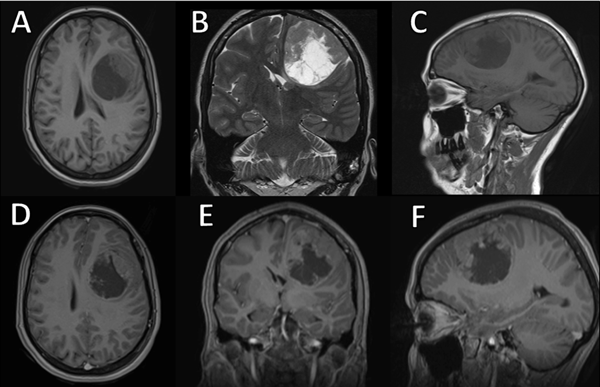

Al examen físico de ingreso se encontraba lúcida sin foco motor ni sensitivo. Como únicos datos positivos, se evidenciaron afasia de expresión, agrafia y alexia. En el estudio de resonancia magnética (RM) cerebral se observó una lesión extraaxial frontal izquierda, de características heterogéneas a predominio hipointenso en secuencia T1 e hiperintensa en T2, sin restricción a la difusión con tenue realce periférico a la administración de contraste endovenoso. Sus mediciones aproximadas eran 5.44 x 4.65 x 5.43 cm. Dicha lesión no producía edema, sin embargo, colapsaba parcialmente el asta frontal del ventrículo ipsilateral y desviaba discretamente las estructuras de línea media hacia el lado contralateral (Figura 1).

Figura 1. Resonancia magnética cerebral prequirúrgica. A) Secuencia axial T1. B) Coronal T2. C) Sagital T1. D-F) Se observa una lesión frontal izquierda redondeada de componente sólido-quístico de aproximadamente 54 mm x 46 mm x 54 mm, de localización extraaxial, que colapsa el ventrículo lateral ipsilateral, con tenue realce a la administración de contraste endovenoso.